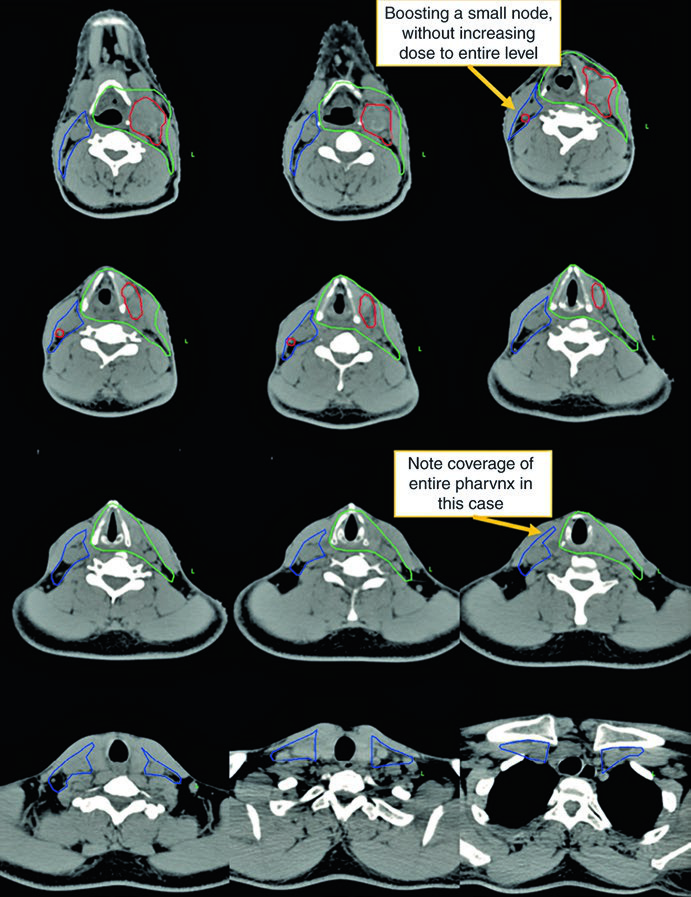

Observe a diferença entre o delineamento no pescoço operado (ipsilateral) e o contralateral. O CTV66Gy (vermelho) cobre o leito cirúrgico de alto risco; o CTV54-60Gy (verde) cobre as mucosas faríngeas em risco de abrigar o primário; e o CTV54Gy (azul) cobre o pescoço contralateral profilaticamente. Essa assimetria reflete o princípio de escalonar a dose conforme o risco real.

A visualização em cortes sagitais (Fig. 10.2) é particularmente útil para confirmar a extensão craniocaudal correta dos volumes de mucosa — nasofaringe, orofaringe e laringe/hipofaringe — e assegurar que não haja lacunas entre os CTVs adjacentes. O isocentro radiográfico serve como referência geométrica para o planejamento.